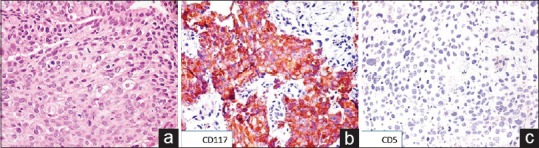

On IHC, both CD117 and CD5 showed diffuse cytoplasmic and membranous positivity [Figures [Figures11 and and2].2]. Two hundred and nine (11.61%) cases showed immunoreactivity for CD5, and 171 cases (9.5%) were positive for CD117. Coexpression of both CD117 and CD5 immunomarkers was seen in 34 (1.88%) cases [Table 1].

| Figure 2:(a) Photomicrograph showing polygonal cells arranged in diffuse sheets with dense eosinophilic cytoplasm and central hyperchromatic nucleus (H and E, ×200). (b) On immunohistochemistry, the tumor cells showed cytoplasmic and membranous positivity for cluster of differentiation 117 (immunostain, ×200). (c) The tumor cells were negative for cluster of differentiation 5 (immunostain, ×200)